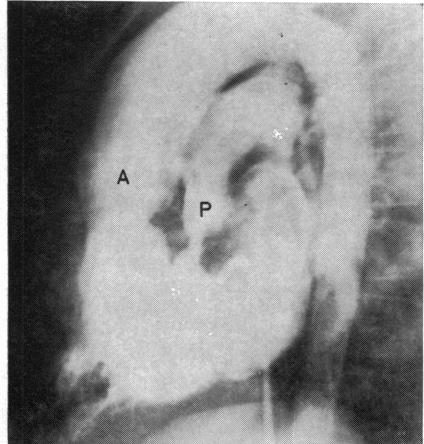

Congenital heart disease--changes in form and function.

Br Heart J. 1979 Jan;41(1):1-22. doi: 10.1136/hrt.41.1.1.